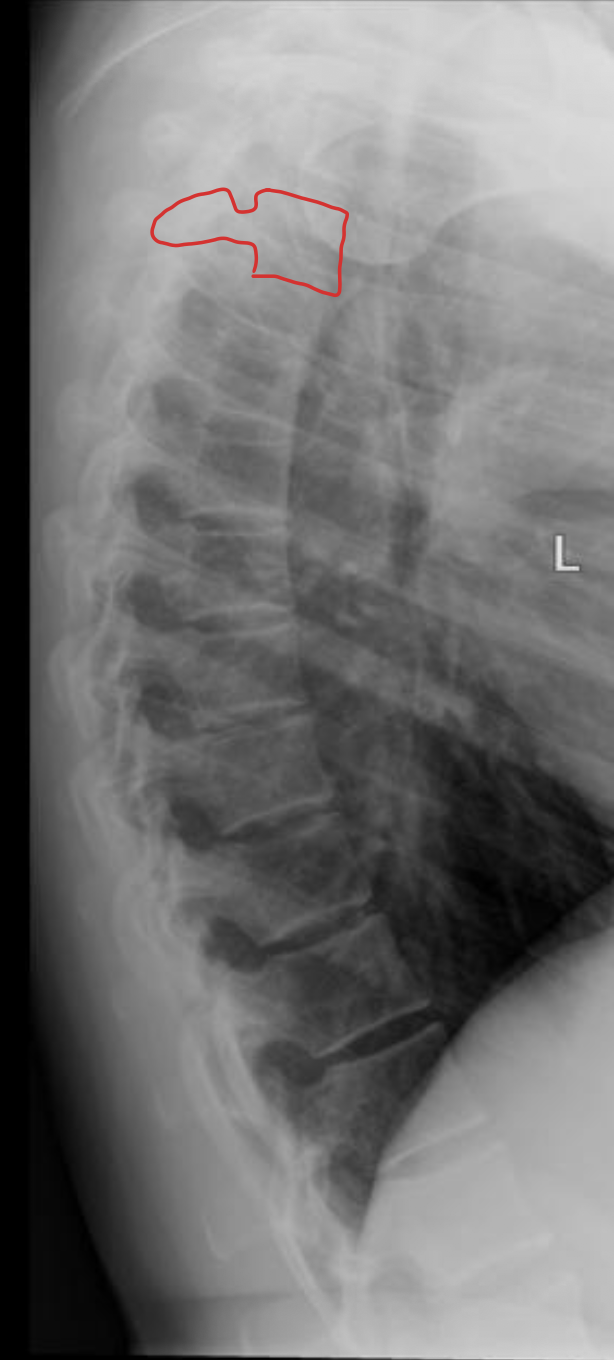

胸椎 12 块

Thoracic vertebrae

胸椎

THORACIC

T1

T2

T3

T4

T5

T6

T7

T8

T9